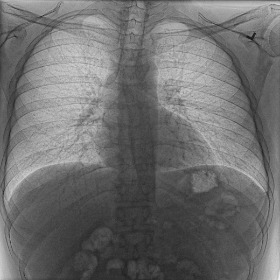

Figure 4: Visual examples of different image enhancement methods across datasets; first and second columns present results from the JSRT and Montgomery County Chest X-ray datasets, respectively, while third and fourth columns show results from the NIH Chest X-ray and CheXpert datasets

4.5 A Visual Assessment

Fig. 4 presents representative visual examples demonstrating the superiority of our method in enhancing vertebral contrast compared to several traditional and learning-based image enhancement techniques. The first and second columns show results from the JSRT and Montgomery County Chest X-ray datasets, while the third and fourth columns display results from the NIH ChestX-ray14 and CheXpert datasets. Across all datasets, the highlighted regions of interest (ROIs) emphasize the spinal areas, where fine structures and subtle details are critical for diagnostic assessment. Our method, XVertNet, consistently reveals clearer and more distinct spinal structures without introducing notable artifacts, preserving both global and local anatomical information. In contrast, traditional methods such as CLAHE [7] and Farbman et al. [19] often fail to enhance these subtle features effectively, either producing over-smoothed results or excessively sharpening noise. Similarly, learning-based methods such as ZSSR [43] and Madmad et al. [68] exhibit difficulties in generalizing across different datasets, leading to either insufficient enhancement or visible artifacts. Zero-DCE [33], although effective for natural images, struggles to adapt to the uniform and low-contrast nature of medical X-rays and was not able to supply clear enough contrast-enhanced vertebral structures.

These visual comparisons underline the clinical relevance of our approach. XVertNet successfully enhances diagnostically important structures, particularly in challenging anatomical regions like the spine, where competing methods either distort the features or fail to sufficiently reveal them. This highlights the value of integrating targeted enhancement strategies that are specifically tailored to the unique characteristics of medical imaging data.